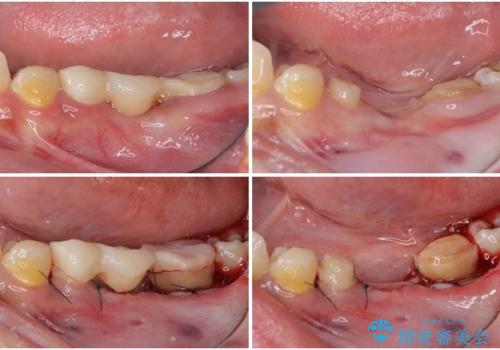

左下の歯は、クラウンを装着するために必要な高さが足りないため、歯冠長を延長するための外科処置を行うこととしました。

根管治療や歯周外科処置後にフルジルコニアクラウンにて補綴治療することとしました。

- 外科手術のため、術後に出血、痛みや腫れ、違和感を伴います